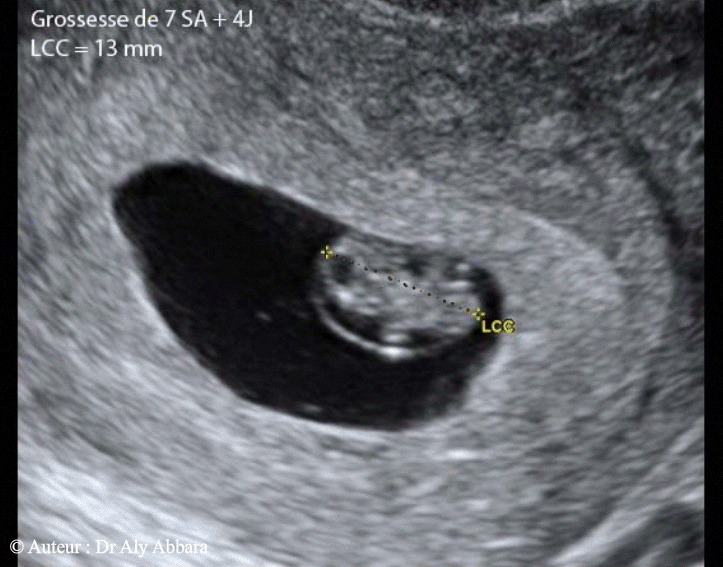

Anatomie Echographique D Une Grossesse De 7 Sa Et 4 Jours

Echo A 7 Semaines Et 4 Jours D Amenorrhee Bidiblog